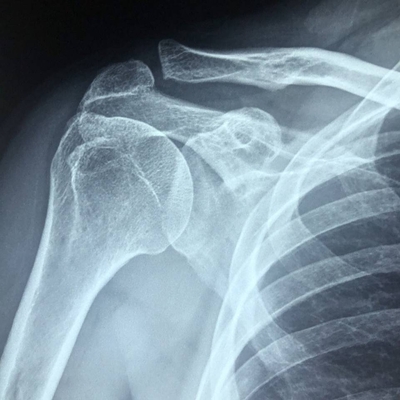

Click on an image below to view more info.